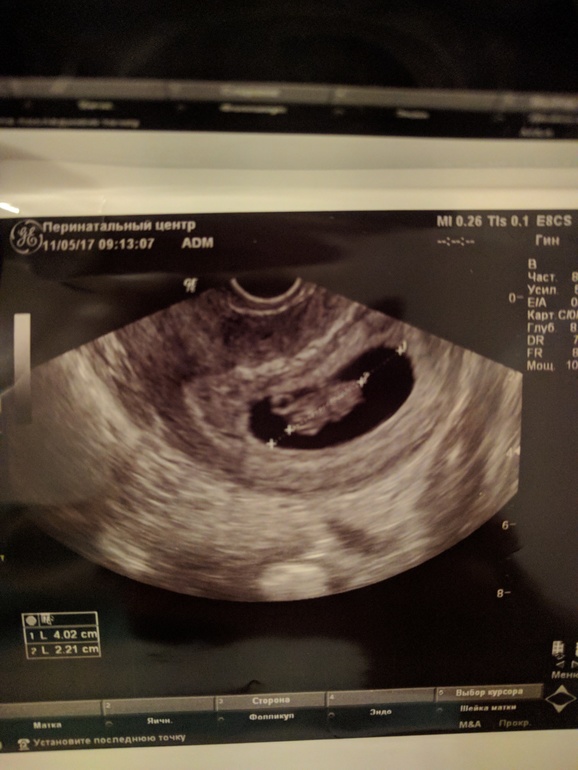

С утра натощак пошла в перинатальный становиться на учёт, сделали УЗИ, кроха хорошо растет, ттт. Эмбриончик уже большой.

Бусинка умница!!! Растёт!!! Правда уже характерная))))

Сразу вспоминаю, как с Лео делала в 7 недель и там была креветочка в 1,25 см. Как же это трогательно